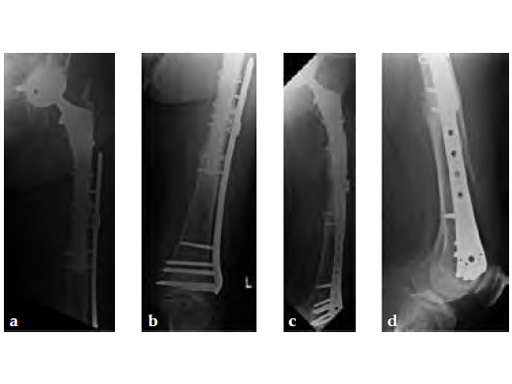

Case 2: A 76-year-old female with a Vancouver type C fracture.